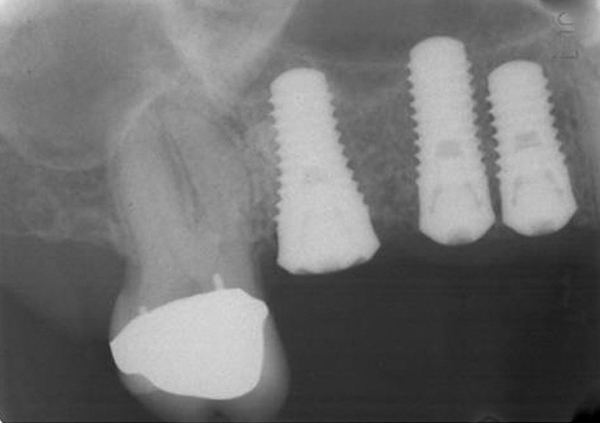

This is probably because the platform of tissue-level implant is 28 mm or 18 mm from the alveolar bone if the smoothrough interface is placed at the crest. Bone level - the titanium is roughened all the way to the top and the implant is placed level with the bone. Bone level dental implants seem to be contraindicated based on my findings simply because there is no neck above the cortical bone crest for vertical bone growth to.

Tissue level - the implant has polished titanium usually about.